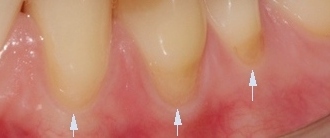

Recesja dziąsłowa to utrata dziąsła, co powoduje odsłonięcie korzenia zęba. Przyczyn jest kilka, między innymi niewłaściwa technika szczotkowania zębów i nieprawidłowe ustawienie zęba (problem ortodontyczny). Korzeń który nie jest pokryty dziąsłem może powodować wrażliwość w czasie jedzenia oraz może stanowić problem estetyczny podczas uśmiechania. Korzeń jest bardziej podatny na powstawanie próchnicy i trudniejszy do oczyszczania szczoteczką na codzień. W większości przypadków najlepszą metodą jest pokrycie korzenia dziąsłem, czyli powrót do fizjologicznych warunków. W tym celu wykonywany jest zabieg chirurgiczny umożliwiający ponowne pokrycie korzenia dziąsłem. Zabieg przeprowadza się po zabiegach higienizacji, ustąpieniu stanu zapalnego dziąsła i uzyskaniu optymalnej higieny jamy ustnej. Poniżej przykład recesji dziąsłowej i stanu po wykonanym zabiegu chirurgicznym pokrycia recesji:

Sytuacja u dzieci jest inna niż u dorosłych. To co może wydawać się recesją dziąsłową w rzeczywistości nią nie jest. Dwa zęby dolne sieczne wydają się “dłuższe” niż sąsiednie co może niepokoić rodziców i sugerować że zostało utracone dziąsło (powstała recesja dziąsłowa). W rzeczywistości występuje “nadmiar” dziąsła na zębach sąsiednich, co jest częstą sytuacją w okresie gdy dziecko rośnie a jama ustna dopiero się rozwija. Taka sytuacja wymaga często tylko obserwacji, konieczności idealnej higieny jamy ustnej, ewentualnie czasem można rozważyć mały zabieg plastyki wędzidełka, jeśli jest takie wskazanie.

Widok z góry na zęby sieczne dolne; widoczne większe wychylenie (ustawienie "na zewnątrz") korzenia jednego z zębów siecznych, przy którym z tego powodu pojawiła się recesja dziąsła. Zabieg chirurgiczny pokrycia korzenia dziąsłem, przeprowadza się po ustawieniu zęba za pomocą aparatu ortodontycznego w pozycji podobnej jak zęby sąsiednie (tzw. wprowadzenie zęba w "kopertę kostną").